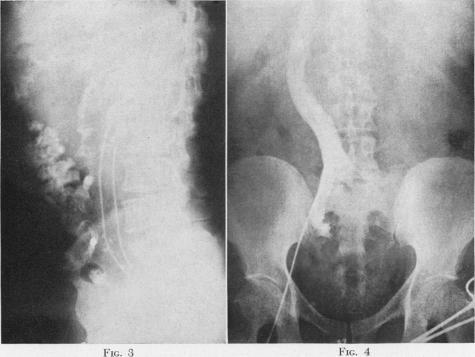

Visualization of the inferior vena cava as an adjunct to diagnosis of retroperitoneal tumors, a case report.

Ann Surg. 1954 Dec;140(6):892-6. doi: 10.1097/00000658-195412000-00016.